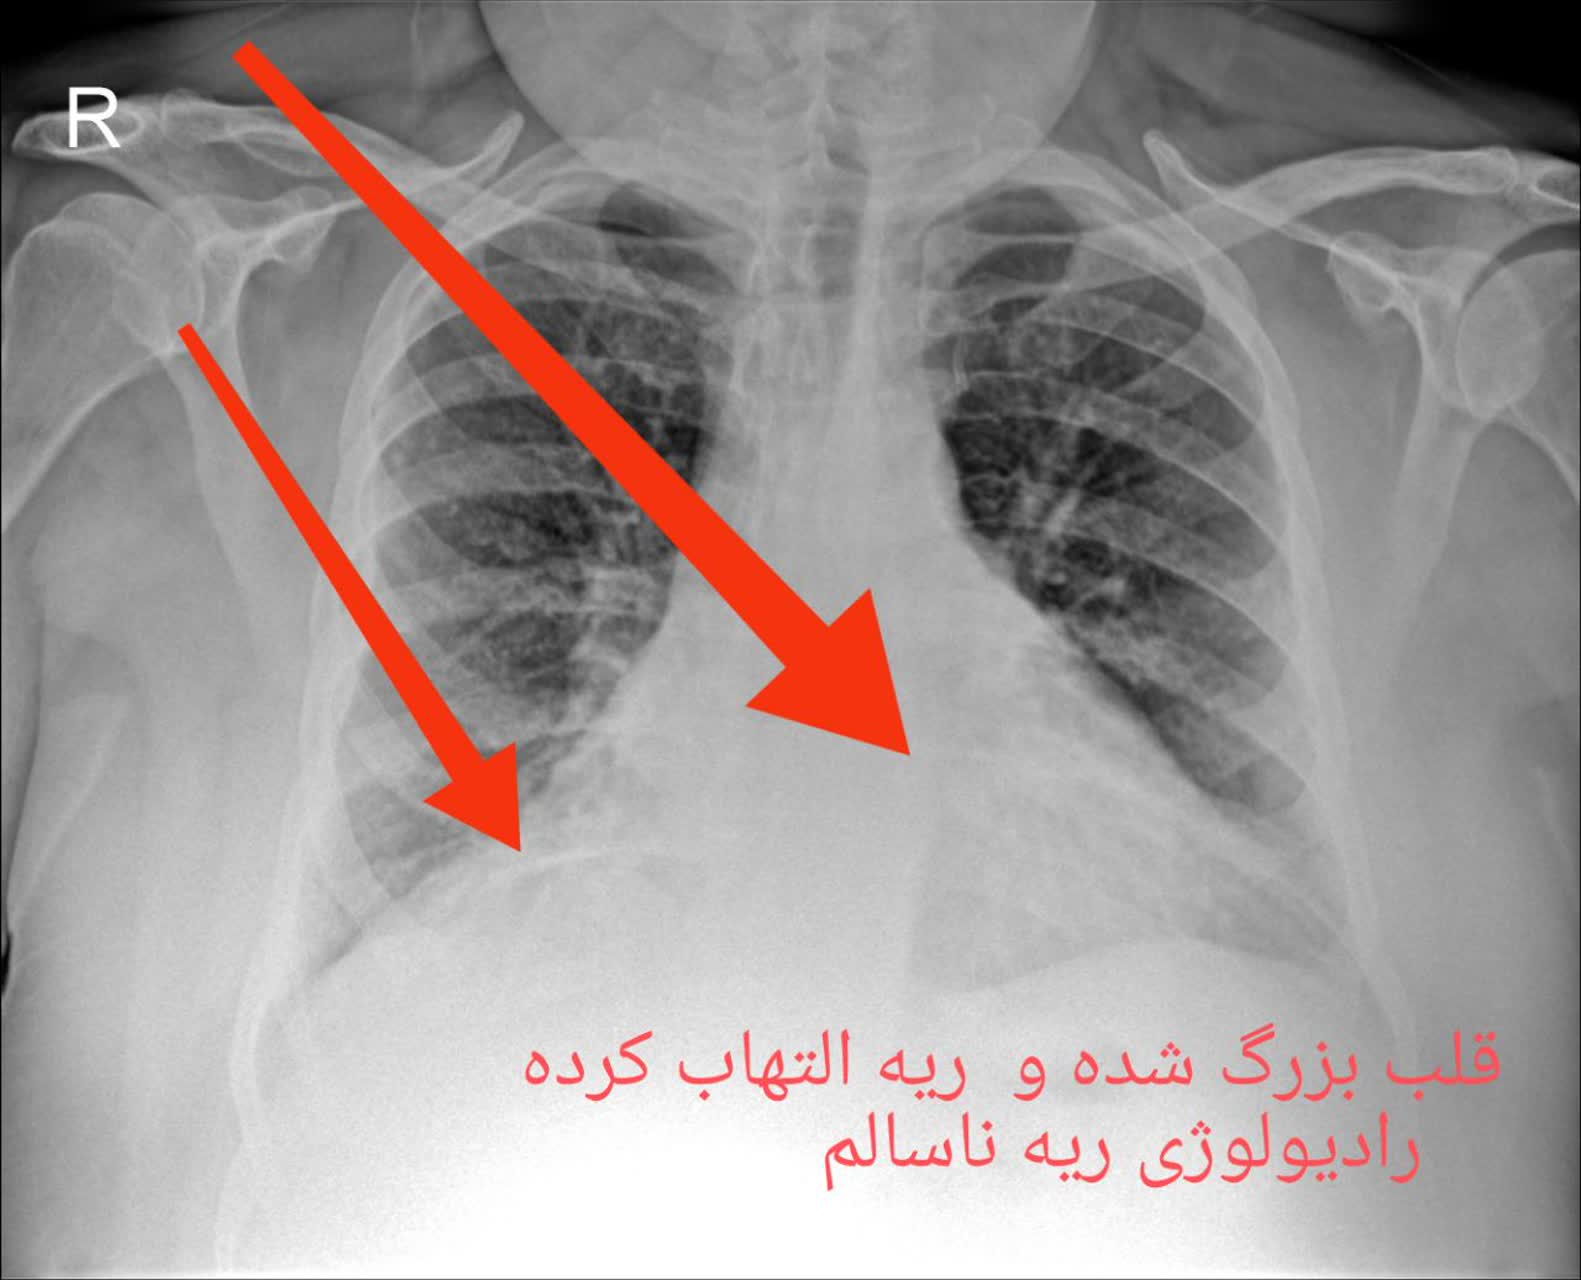

2. التهاب ریه: شامل التهابهای مختلفی از جمله عفونتهای تنفسی و نیز التهاب ریههای مزمن مثل بیماری مزمن انسدادی ریه (COPD) میشود.

مقایسه عکس ریه سالم و ناسالم

در عکس ریه سالم و ناسالم، تفاوتها معمولاً با چشم غیرمسلح نیز مشهودند. ریه سالم تصویری یکنواخت و شفاف دارد، با خطوط ریوی طبیعی و بدون سایه یا توده. در مقابل، ریه ناسالم ممکن است سایههای غیرطبیعی، نواحی سفید شده (indicative of consolidation)، خطوط پررنگتر ناشی از فیبروز یا تودههای نامنظم را نمایش دهد. تشخیص این تفاوتها توسط پزشک رادیولوژیست، نیاز به تجربه و تجهیزات باکیفیت دارد، چیزی که در خدمات رادیولوژی ریه در منزل تهران و رادیولوژی ریه در منزل کرج فراهم شده است.